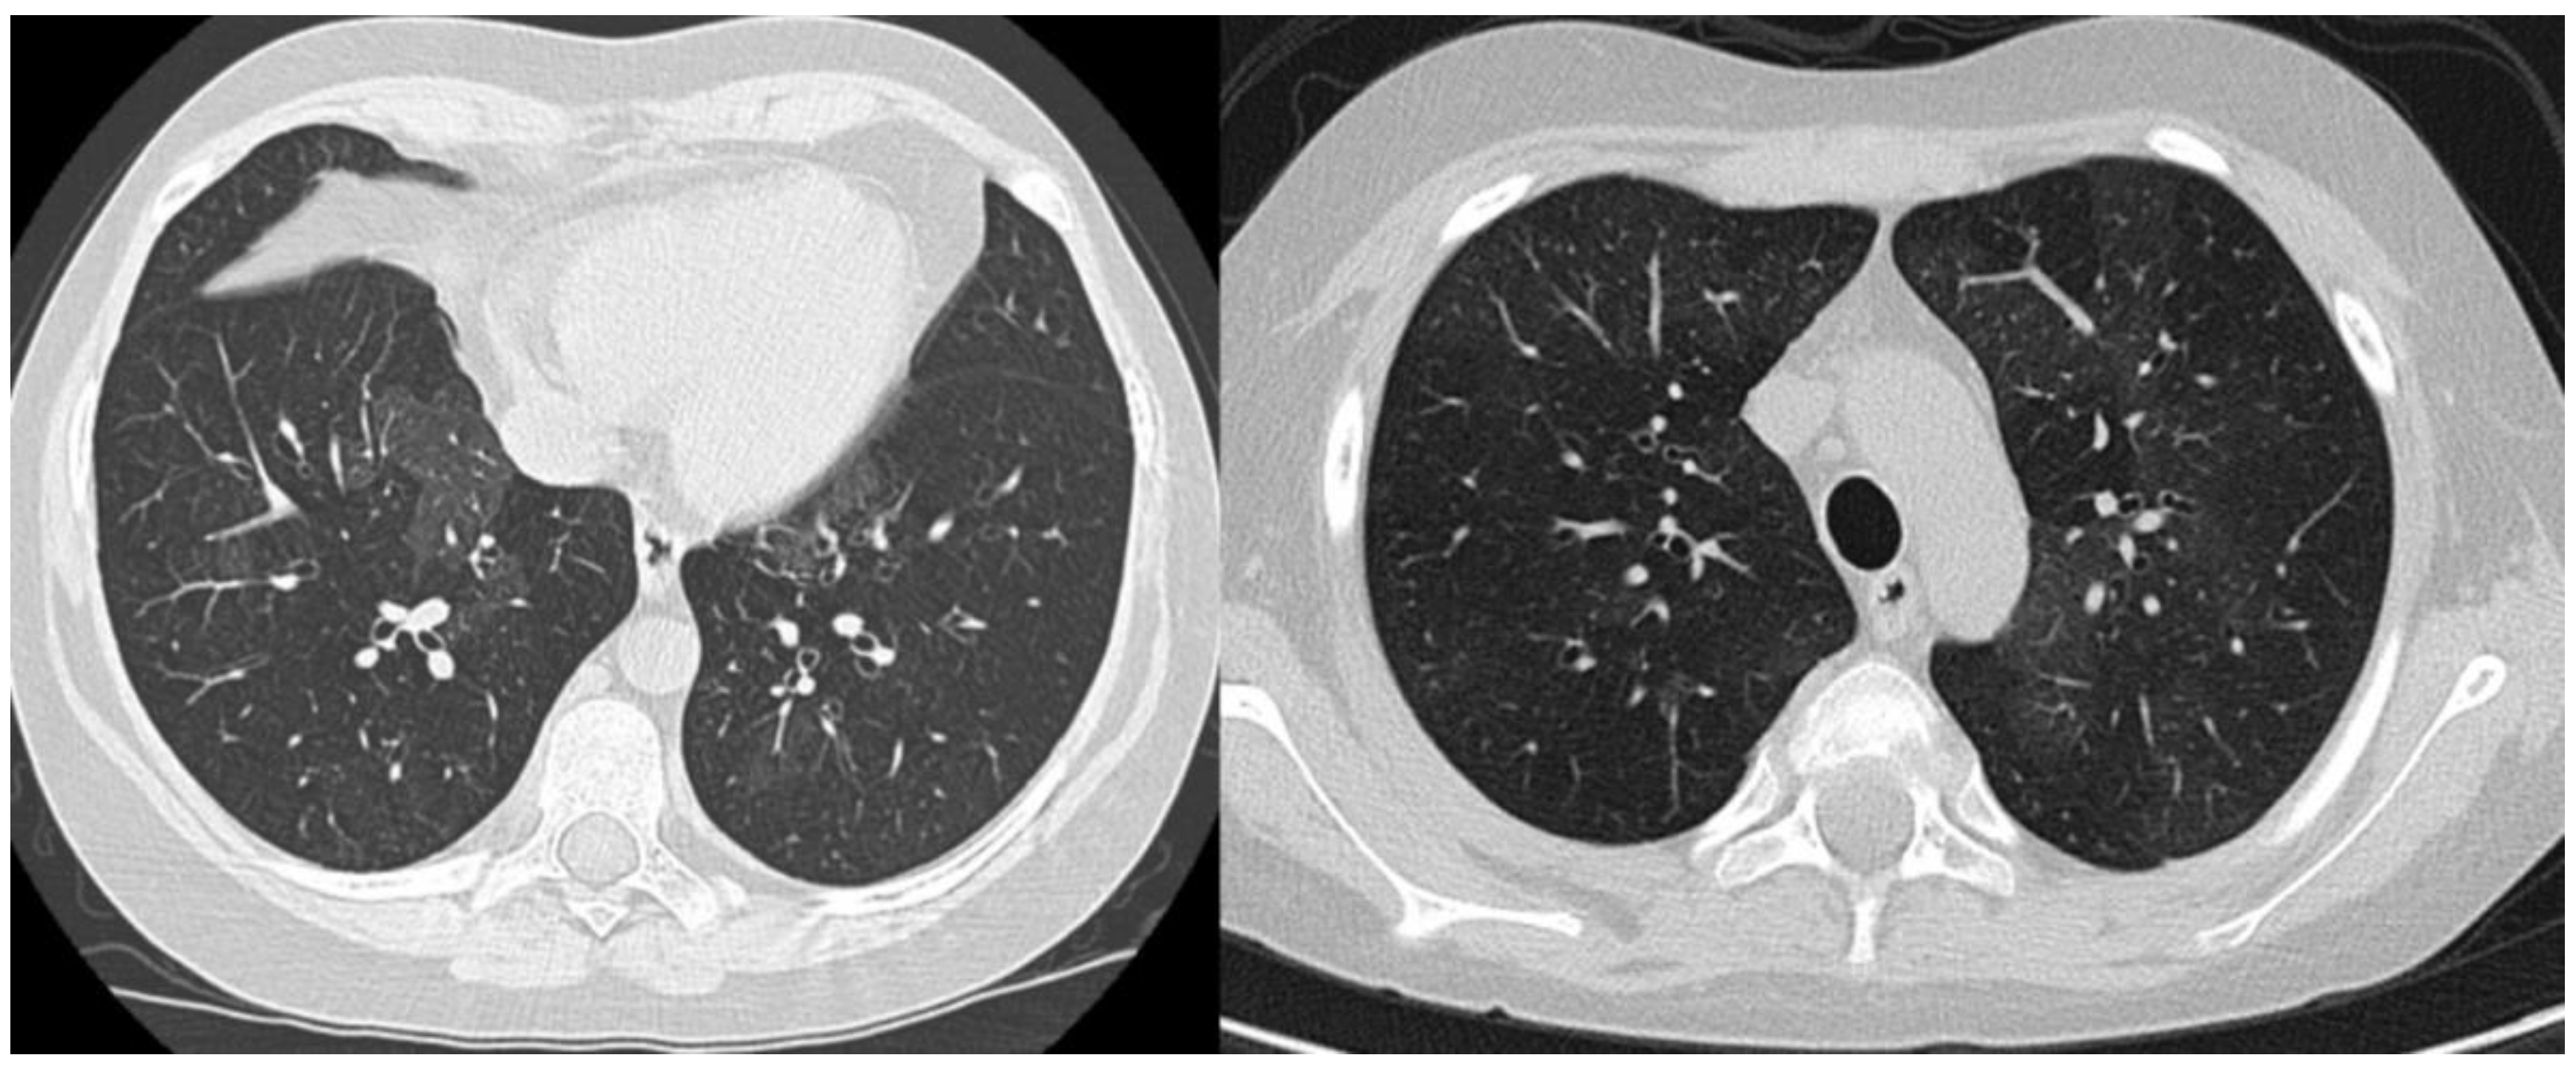

3. Case Report